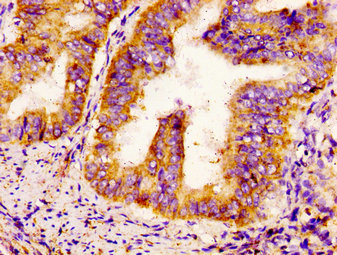

IHC image of CSB-PA613605LA01HU diluted at 1:300 and staining in paraffin-embedded human endometrial cancer performed on a Leica BondTM system. After dewaxing and hydration, antigen retrieval was mediated by high pressure in a citrate buffer (pH 6.0). Section was blocked with 10% normal goat serum 30min at RT. Then primary antibody (1% BSA) was incubated at 4°C overnight. The primary is detected by a biotinylated secondary antibody and visualized using an HRP conjugated SP system.